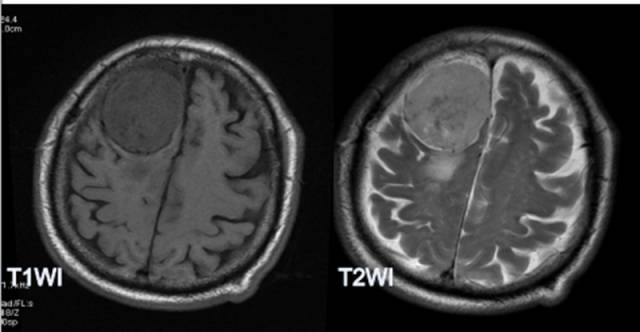

病例1:

MR平扫病灶呈等高信号,TE=35ms,MRS波谱显示Cho、Glx、GSH、Gly峰升高,Cr峰降低,NAA峰消失,并见Ala峰;TE=144ms,显示Ala峰倒置。

病例二:

MR平扫病灶呈等信号,增强病灶呈较均匀强化;MRS病灶侧波谱显示Cho峰明显升高,Cr、NAA峰未显示,并见Glx、GSH峰和倒置的Ala峰。